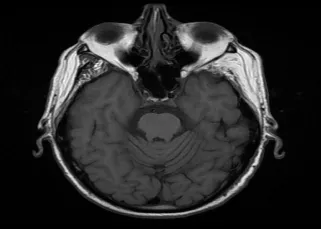

Clinical Studies Guerbet Clinical Studies Clinical Case Studies as seen in Applied Radiology Neurological and Orbital Involvement of Systemic IgG4-related Sclerosing Disease DOWNLOAD Atypical Teratoid Rhabdoid Tumor of the Oculomotor Nerve DOWNLOAD Pediatric Pineoblastoma DOWNLOAD